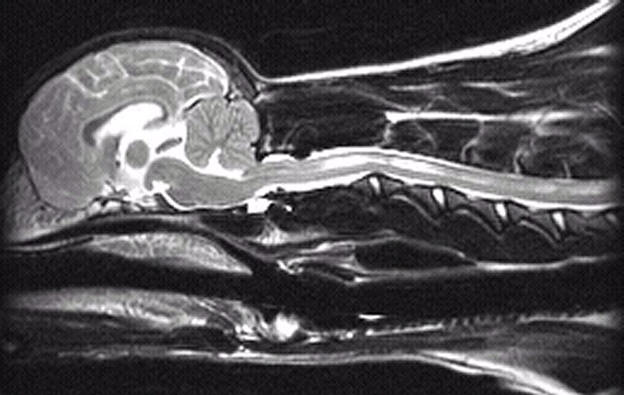

8 years old

No symptoms of SM whatsoever

Very mild malformation, slight

squashing/pinching of cerebellum

No herniation

Medulla almost normal

Very slight dilatation of central canal

in one tiny area

3 years old

No symptoms of SM

Mild malformation, slight

Probable mild dilatation of the central

canal

Medulla kinked/squashed

You can also see the vertebrae. They are the white lines that look almost like pointers

underneath the spinal cord. Three are visible.

One (C1) is below the cerebellum where

the spinal cord begins

The other two are further back--C2 and C3